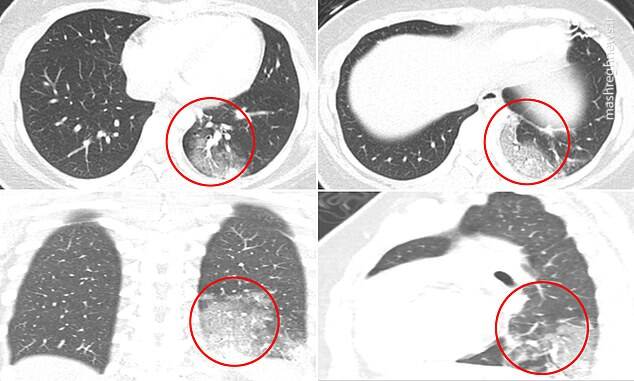

mshrgh.ir/1071375 کد خبر 1071375 تاریخ انتشار: ۲۲ اردیبهشت ۱۳۹۹ - ۰۸:۰۳ ۰ نظر چاپ عکس و فیلم عکس/ سی تی اسکن از کودکان مبتلا به کرونا تصاویر سی تی اسکن از کودکان مبتلا به کرونا در بوستون آمریکا نشان می دهد بیش از نیمی از آنها دچار التهاب شدید ریه هستند. اخبار مرتبط عکس/ تمرین ورزشکار قایقرانی در خانه فیلم/ اروپا در صف کیت تشخیص کرونای ایرانی فیلم/ آخرین آمار مبتلایان به کرونا در جهان عکس/ تمرین ورزشکاران ایرانی در شرایط کرونایی فیلم/ نکات کلیدی استفاده از ماسک در مترو عکس/ درگیری پلیس با مخالفان قرنطینه عکس/ تعظیم تکنولوژی، اینترنت و آموزش مجازی! عکس/ همافزایی گروههای جهادی در پویش ۱۴۴۱ عکس/ دیدار بستگان از طریق جرثقیل عکس/ به وقت افطار عکس/ تظاهرات معترضان به قرنطینه در آلمان عکس/ تب سنجی قبل از جلسه دادگاه عکس/ مقاومت یک کودک در برابر انجام تست کرونا عکس/ مرحله دوم کمک مومنانه در آذربایجان برچسبها ویروس کرونا کودکان سی تی اسکن بیماری ریه آمریکا